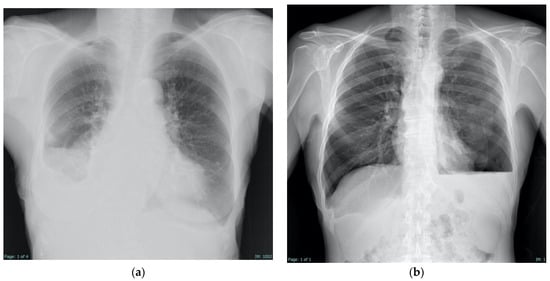

| Key radiologic findings |

|